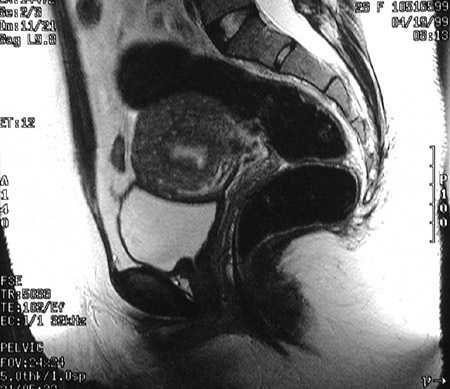

In this fast spin echo T2 weighted MRI scan of the pelvis in sagittal view, the uterus demontrates abnormal low T2 signal intensity with obliteration of the junctional zone consistent with adenomyosis. The uterus is enlarged.